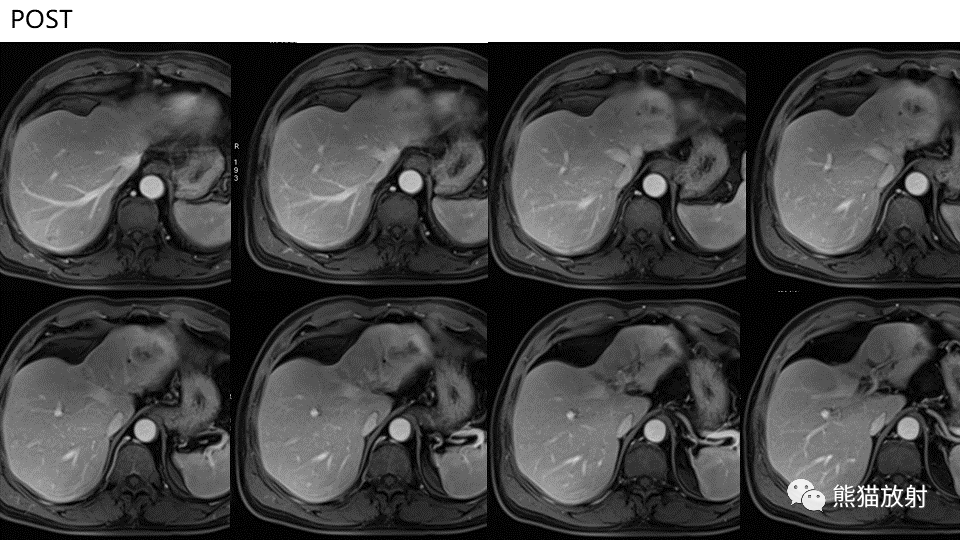

【PPT】肝内胆管细胞癌 VS 肝脓肿